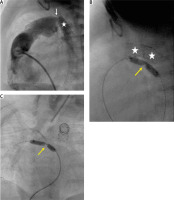

Preceding a stent implantation, a 7F sheath was inserted into the pulmonary artery and subsequent angiography showed the size and length of the DA and made it possible to establish a landing zone which started at the origin of the left pulmonary artery (LPA). Balloon expandable stents (Palmaz Genesis) ranging in size from 7 mm/12 mm to 10 mm/19 mm were deployed into the arterial duct. Unfortunately, if the stent was too short (less than 15 mm) or too narrow (less than 8 mm), the procedure was complicated with stent dislodgment or DA proximal or distal stenosis with the need for additional interventions. Another crucial problem was obturated retrograde flow into the aortic arch due to the stent or isthmus stenosis limiting the coronary and cerebral flows (Figures 3–5).

Figure 3

Percutaneous arterial duct stent deployment and banding balloon plasty. A – Pulmonary artery angiography in lateral view in patient 6 following Palmaz Genesis 8 mm/12 mm stent deployment into the arterial duct (white star) with proximal duct stenosis (white arrow). B – Left pulmonary artery band balloon plasty with an indentation at the tight band (yellow arrow). White stars indicate 2 wide stents implanted into the stenotic arterial duct. C – Right pulmonary artery band balloon plasty with an indentation at the tight band (yellow arrow)

Figure 4

Arterial duct stent implantation during hybrid procedure. A – Pulmonary artery angiography during hybrid procedure performed through the sheath introduced into the artery. Tight bands over the pulmonary branches (yellow arrow). Wide arterial duct (white star). B – A stent Palmaz Genesis 8 mm/12 mm (white arrow) implanted into the proximal part of the arterial duct. Distal arterial duct stenosis (red arrow). C – Arterial duct angiography following second Palmaz Genesis 8 mm/12 mm stent deployment (dash line) and wide antegrade flow into the descending aorta and obstructed retrograde flow into the aortic arch through the stenotic isthmus (white arrow)